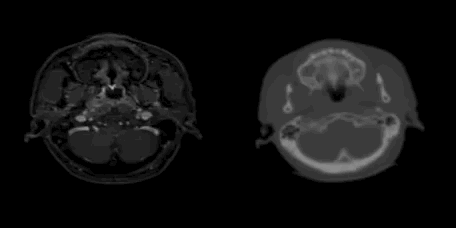

给定参考图像 I_fI_f 和浮动图像 I_mI_m ,所谓的配准就是寻找一个图像变换TT,将浮动图像I_mI_m变换到和 I_fI_f 相同的坐标空间下,使得两个图像中对应的点处于同一坐标下,从而达到信息聚合的目的。在医学图像配准中,最常见的例子便是将同一个部位的CT图像变换移动到与MRI图像的位置相同,如下图:

添加图片注释,不超过 140 字(可选)